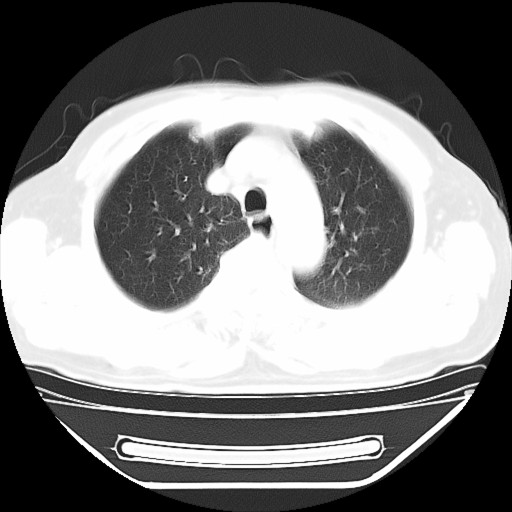

以下是引用hhcckk在2009-5-29 10:34:00的发言:[br]左下肺片絮状边缘模糊影,考虑感染,建议治疗后复查[br]